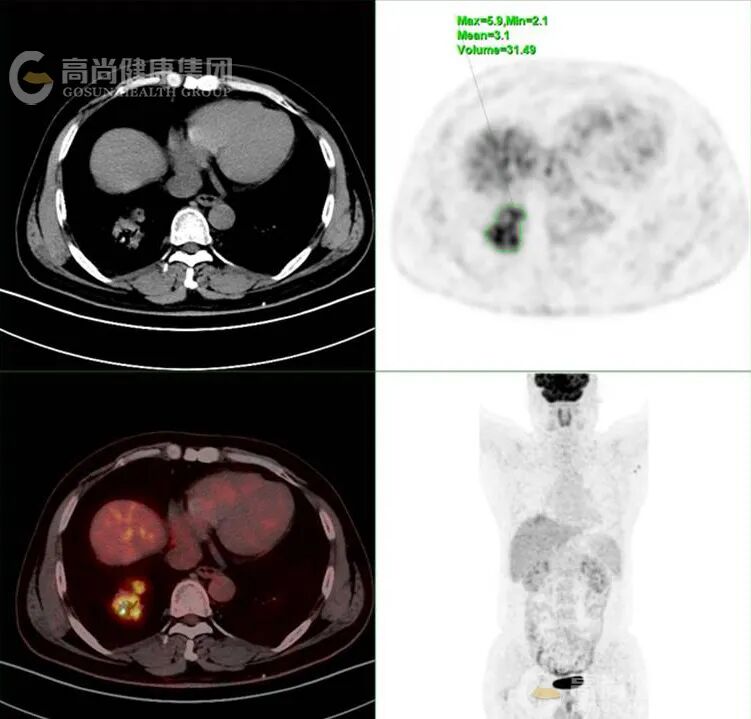

代谢活性特点:MALT 淋巴瘤作为低度恶性肿瘤,FDG 代谢常呈轻度至中度增高,SUVmax 范围多为 2.6-8.3(中位约 6.0),低于侵袭性淋巴瘤类型。

鉴别诊断价值:PET/CT 全身成像有助于区分原发性肺淋巴瘤与继发性肺部受累,且显示大多数肺部 MALT 淋巴瘤病灶存在 FDG 放射性摄取增高,但需注意与其他可导致放射性浓聚的肺部疾病(如肺癌、炎症、结核等)鉴别,需密切结合 CT 影像特征。

以下是肺部 MALT 淋巴瘤 PET/CT 典型表现的总结表格: